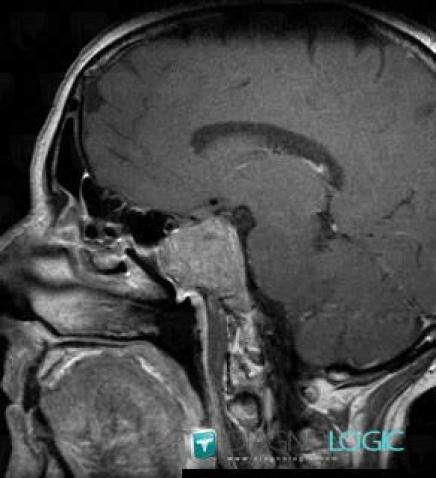

Macroadénome hypophysaire, Hypophyse et région parasellaire, IRM

Voici les informations spécifiques à l'image clé ci dessus:

- Diagnostic Macroadénome hypophysaire, Localisation(s) Hypophyse et région parasellaire, comportant les gammes Lésion du sinus caverneux